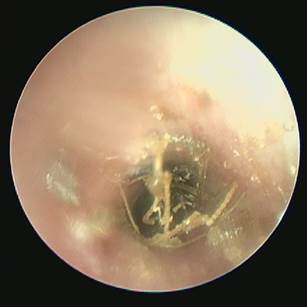

What is this?

Foreign body otitis

Grass seeds most common

Often stimulate violent response in the affected individual – sudden onset

Check the other ear!

Can be hidden in discharge and migrate into middle ear

Painful - chemical restraint is essential in most.

Grass seeds are most common in the summer

Beware the hair that looks like a grass seed and vice versa